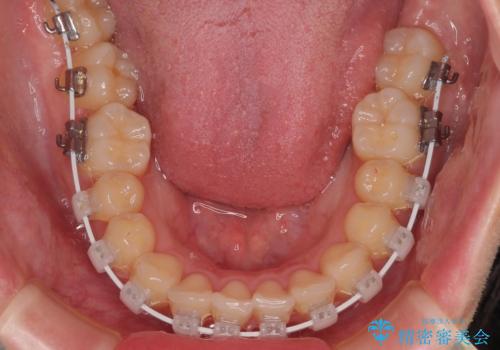

- 矯正装置

- 審美装置

- 治療期間

- 1年1ヶ月

- 上下前歯のデコボコを気にして来院された患者様です。

ワイヤー矯正でもマウスピース矯正でも可能でしたが、短期間で、自身の手を煩わせることなく治療を行いたいとのことで、ワイヤー装置にて矯正治療を行うこととしました。

舌の突出癖により、出っ歯仕上がりとなる可能性がありましたが、舌のトレーニングを頑張っていただき、1年強で終えることができました。